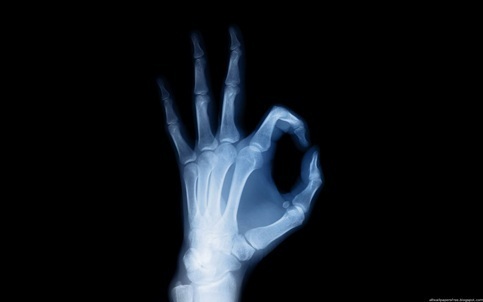

Рентгеновские вспышки, испускаемые трубкой, проходят через туловище лица и также проецируются на специальную пластину - почти так же, как в фотоаппарате.

Элемент, расположенный в костях позвоночника, обычно проходит несколько рентгеновских вспышек. По этой причине на фотографии, полученной в ходе опроса, останки будут самыми красочными - белоснежными, поэтому, как и в этой области на обложке, как правило, взглядов будет меньше.

Жир, вода в организме, мышцы и крепежные материалы привлекают меньше внимания - они отражены на снимке сероватыми цветами.

Воздушное пространство меньше поглощает обычные рентгеновские вспышки. Непосредственно по этой причине заполненные им полости, такие как простые, являются самыми черными на изображениях.

Рентгенологическое исследование позволяет получить двумерное представление туловища, в котором останки становятся наиболее чистыми зонами, а полости, содержащие воздушное пространство, становятся черными.